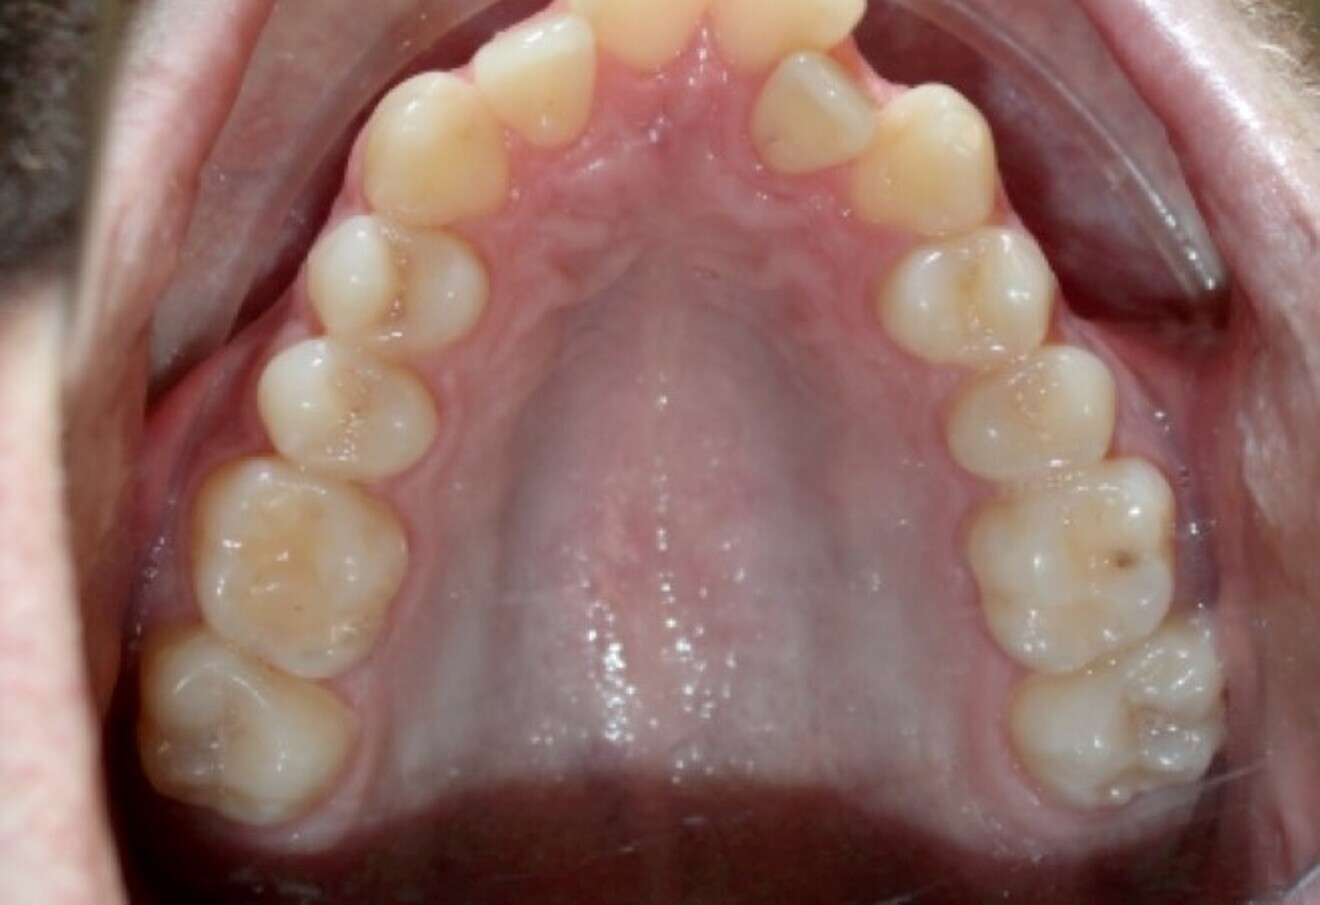

Fig. 18b: Class II malocclusion requiring fixed appliance treatment. (a) Lateral view. (b) Occlusal view.